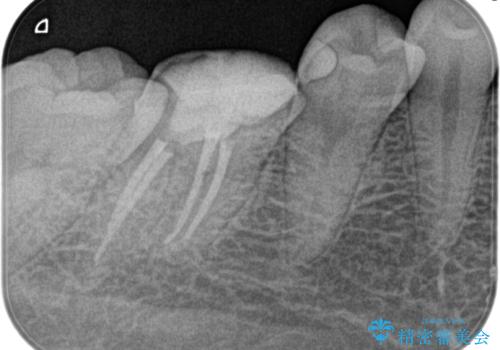

- 4日前から噛んだ時に痛むことを主訴に来院された患者様です。

歯髄壊死/症候性根尖性歯周炎の診断のもと、根管治療を行なっております。

- 精密根管治療(イニシャルケース,大臼歯):122,000円、ファイバーコア:22,000円費用は治療当時の料金となります